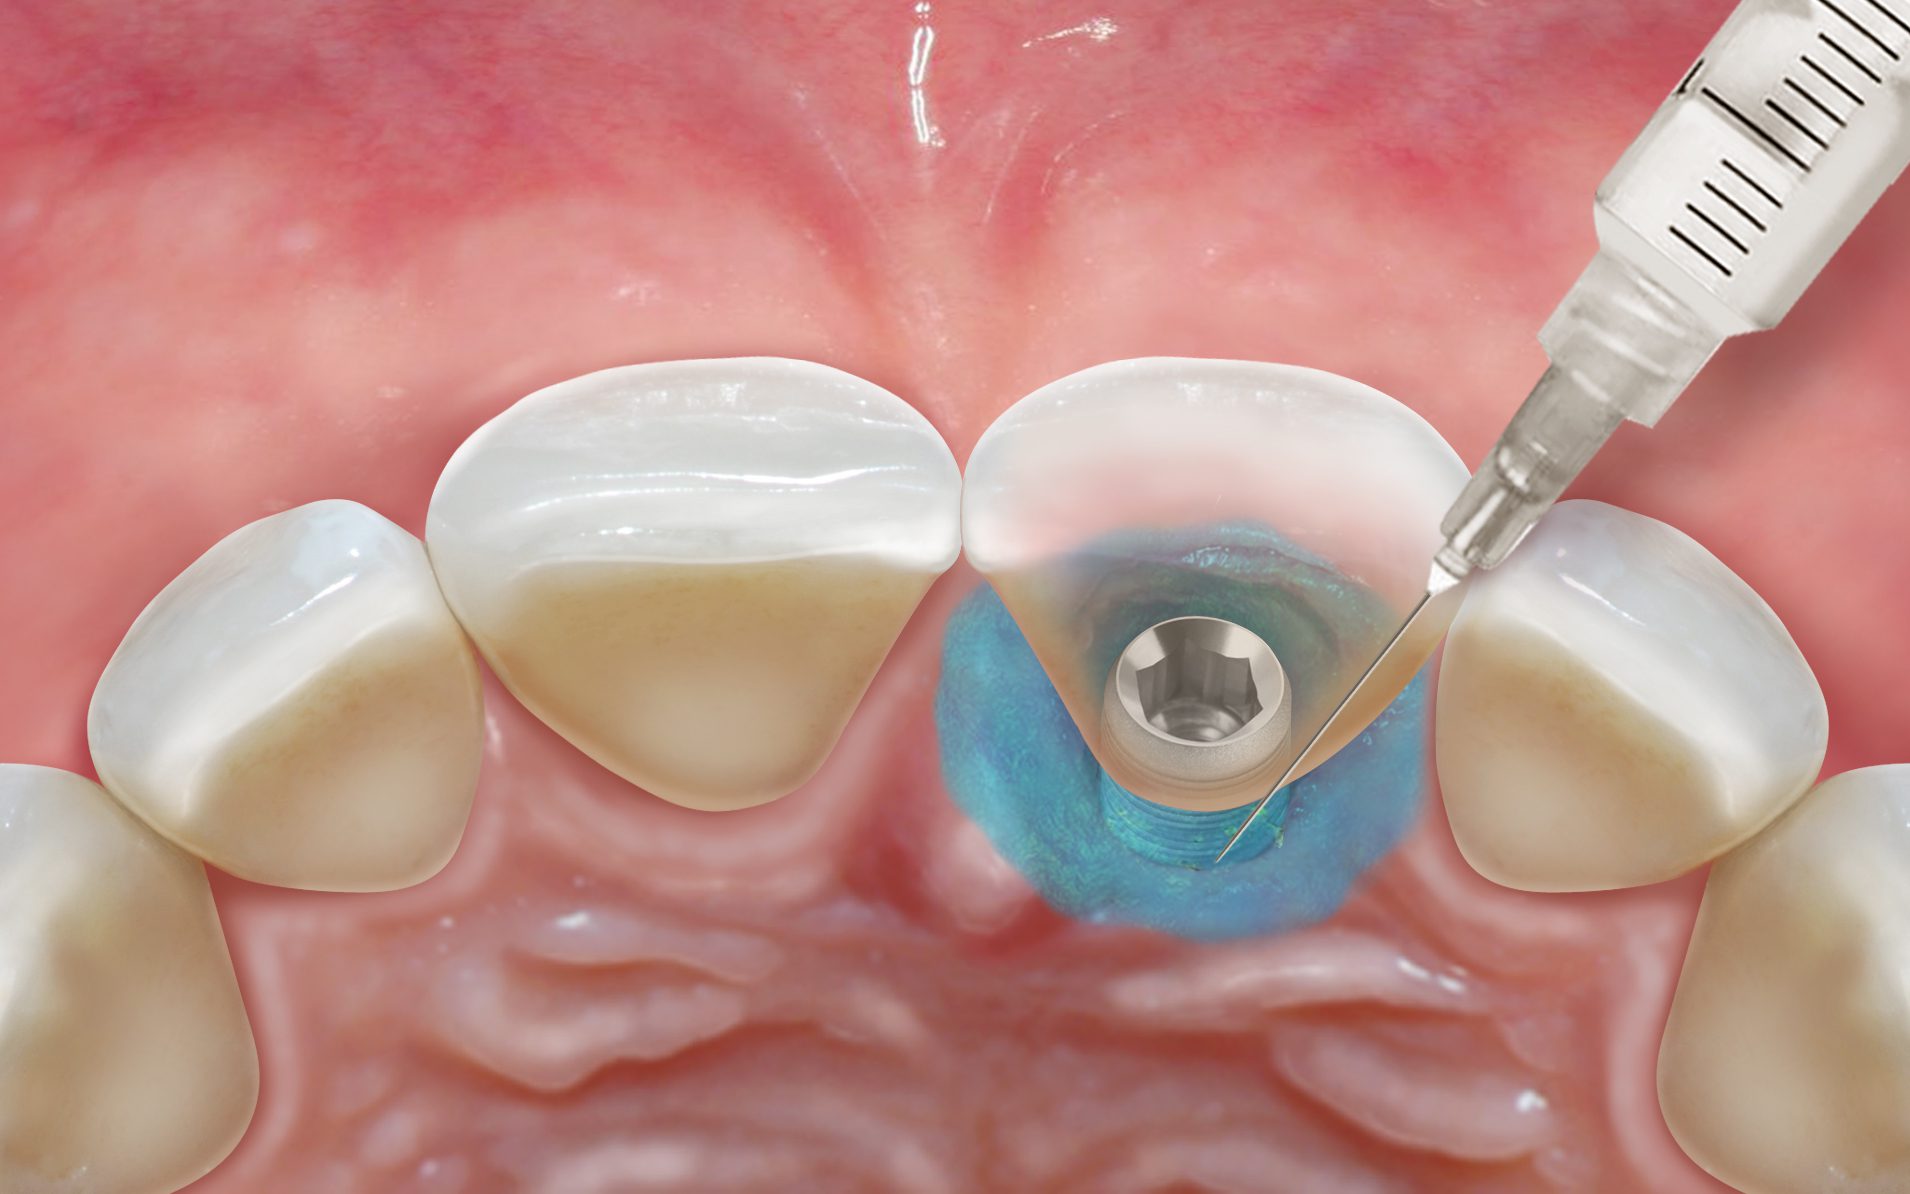

2) Sealing technologie: Na de reiniging wordt een geavanceerde bio-compatibele sealer genaamd Hyadent BG aangebracht. Deze sealer vormt een beschermende barrière die helpt de pockets te isoleren van bacteriële herinfectie. De sealer is ontwikkeld om de natuurlijke genezing te ondersteunen en bevordert de regeneratie van zowel zacht als hard weefsel rondom de tanden en implantaten.

Aanbrengen van Hyadent BG hyaluronzuur in de parodontale pocket

Hieronder laten we een perfecte casus zien van een verontreinigd implantaatoppervlak dat is glad gemaakt met behulp van NiTi brushes en Perisolv. Daarna is er opgebouwd met hyaluronzuur, smartgraft en een membraan. Tot slot heeft de behandelaar het geheel twee maanden laten genezen met een healing abutment. De resultaten op de foto's hieronder spreken voor zich.